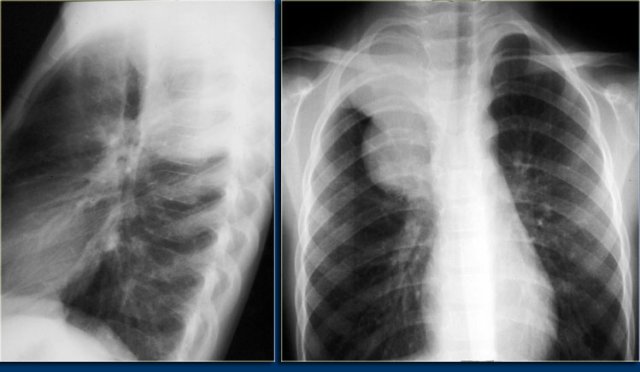

Hodgkin lymphoma Hodgkin lymphoma

The chest film shows the typical features of Hodgkin lymphoma, e.g., an anterior mediastinal mass.

The CT-images of the same patient show a large soft tissue mass in the anterior mediastinum, which arises in the thymus.

There is associated paratracheal adenopathy (arrow).